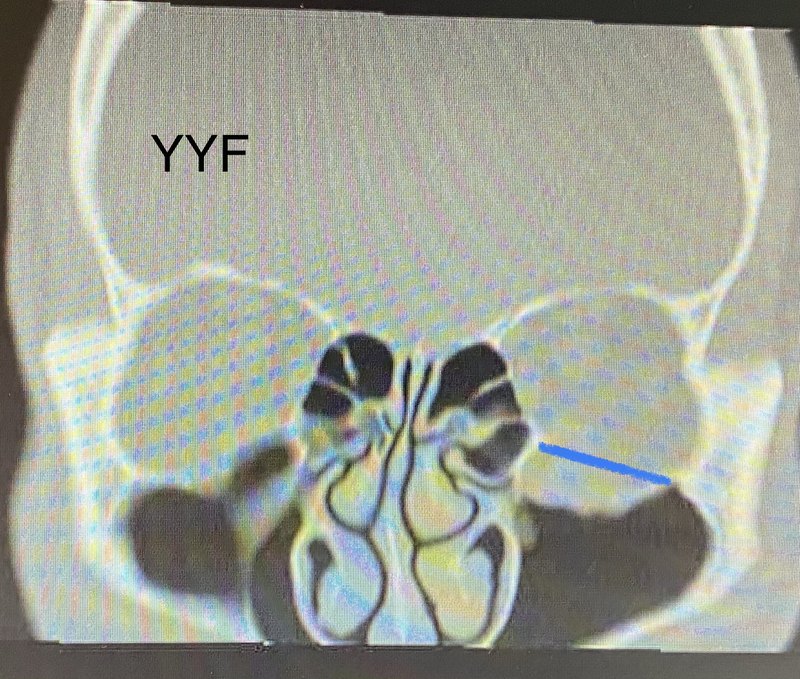

305.眼眶骨折系列之五:可吸收材料治療兒童眼眶內(nèi)側(cè)壁骨折&合理的材料選擇很重要

患者為十余歲的兒童,外傷后CT拍攝顯示眼眶內(nèi)側(cè)壁骨折。盡管影像學(xué)報告上提示骨折,但是作為眼眶專業(yè)醫(yī)生,需要自己具備讀片判斷能力,畢竟工作重點和影像學(xué)醫(yī)生不同,臨床經(jīng)驗和大量病例的隨訪,會幫助判斷什么樣的骨折(尤其是“不大不小”的那一類)最終需要干預(yù)。本例CT顯示骨折移位尚可且為內(nèi)壁,與下壁骨折容易受重力影響不同,同等范圍移位下壁骨折往往凹陷更為明顯。因此結(jié)合家屬想法,先保守治療觀察但是在隨訪一段時間后,患者依舊出現(xiàn)眼球內(nèi)陷,外觀有差異。除了眼眶腔擴(kuò)大的因素以外,個別患者外傷后脂肪因血供受損萎縮,可能也是原因之一。眼球內(nèi)陷不僅造成外觀上的異常,給患者帶來一定心理的影響。由于眼球不在一個平面上,所導(dǎo)致的視疲勞,也會困擾患者。最終選擇可吸收材料治療骨折,其原因有二:第一,對于兒童眼眶發(fā)育的影響,可吸收材料相對更??;第二,患者的骨折范圍有限,符合手術(shù)指征。需要指出的是:臨床上并非所有眼眶骨折都可以用可吸收材料解決。由于骨折手術(shù)的最終目的既包括功能的恢復(fù),也包括飽滿度外觀的矯正。合理選擇材料其實非常重要。患者術(shù)后屬于飽滿度過矯,為術(shù)后正常水腫的原因,可吸收材料并不顯影,在影像片上隱約可見。后期經(jīng)過功能鍛煉。術(shù)后的早期復(fù)視會絕大部分會逐步恢復(fù)??晌詹牧舷鄬r錢相對昂貴,但并不代表適用于所有類型的骨折,也并非貴即是好。不同的醫(yī)院,不同的醫(yī)生,可能會有治療策略上的差別。而最終的治療效果,是最終唯一的金標(biāo)準(zhǔn)。在術(shù)前的溝通當(dāng)中,經(jīng)常會遇到患者不放心的問你們有可吸收材料嗎?目前市面上所有的骨折相關(guān)材料,包括鈦網(wǎng)、人工骨片,鈦網(wǎng)和人工骨片的復(fù)合材料,可吸收材料,不同廠家,各種型號,各種尺寸,各種厚度應(yīng)有盡有。作為專業(yè)的眼科醫(yī)院做到備貨齊全是最基本的要求。根據(jù)病情選擇合適的材料,是除了手術(shù)技巧以外的關(guān)鍵因素。